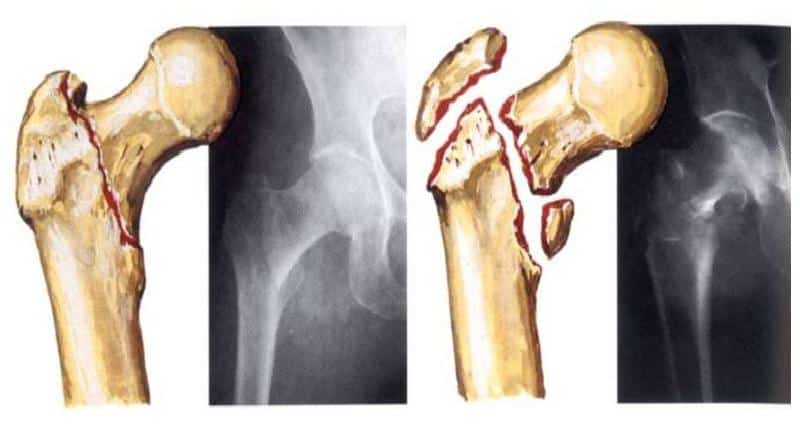

Оскольчатый перелом бедра

Для формирования полной клинической картины перелома, пострадавшего направляют на рентгенографию, в результате которой определяют точное положение костей, положение осколков и их количество. Информацию о состоянии мягких тканей можно получить после процедуры магнитно-резонансной томографии или компьютерной томографии.